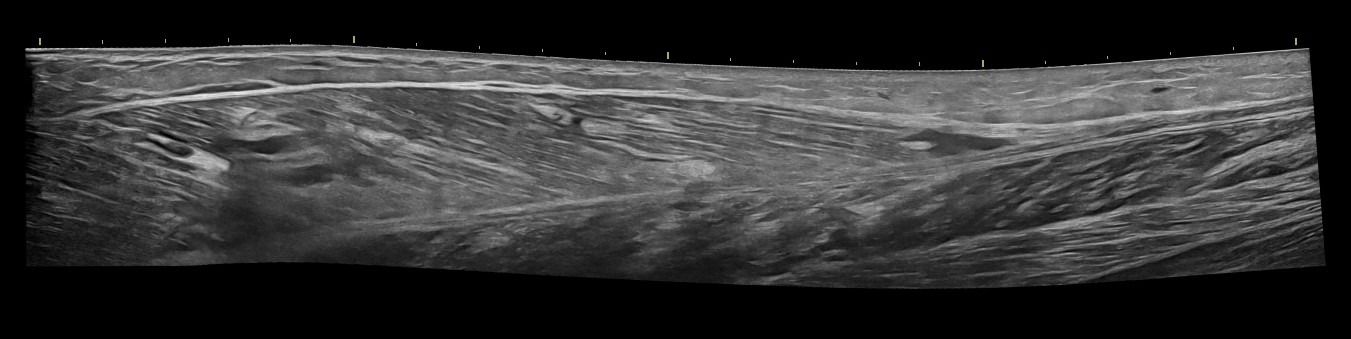

- Κατηγοριοποίηση (Grading) Θλάσεων Μυών: Το Υπερηχογράφημα Μυών μπορεί να αποτελέσει ιδανικό εργαλείο για την ανίχνευση και εκτίμηση της έκτασης μυϊκών θλάσεων μετά από τραυματισμό ή άλλα μυϊκά προβλήματα.

- Διάγνωση Μυϊκών Βλαβών: Το Υπερηχογράφημα Μυών επιτρέπει την αναγνώριση μυϊκών παθήσεων όπως τα αιματώματα, τα λιπώματα, τα νεοπλάσματα και η σημειολογία ασβεστοποιού μυοσίτιδας.